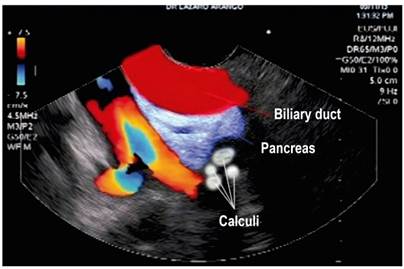

Calcifications or calculi in secondary branches (Figure 1)

Figure 1 Calculi in the parenchyma of the pancreas and branches seen by Fujinon’s linear endosonography (image edited by the Union of Surgeons SAS, Lázaro Arango).